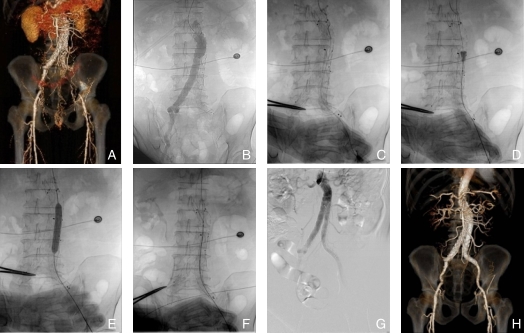

图2 男性患者,EVAR术后3个月出现右侧下肢间歇性跛行,考虑右侧ILO A:术前腹主动脉CTA;B:术中腹主动脉造影;C:导丝通过右侧ILO段;D:8 F Rotarex导管进行PMT;E:对髂支内及EIA病变段进行球囊扩张;F:髂支近端植入自膨式BMS,远端植入外周覆膜支架;G:造影显示右侧髂支恢复正常血流;H:出院时复查主动脉CTA显示腹主动脉双侧髂动脉管腔无明显狭窄Fig.2 A male patient presented with intermittent claudication in the right lower limb 3 months after EVAR, indicating right-sided ILO A: Preoperative abdominal aortic CTA; B: Intraoperative abdominal aortic angiography; C: Guidewire passing through the right-sided ILO segment; D: 8 F Rotarex catheter performing PMT; E: Balloon dilation of the diseased segments in the iliac limb and EIA; F: Self-expanding BMS implanted in the proximal iliac limb, and a peripheral covered stent implanted in the distal segment; G: Angiography showing normal blood flow in the right iliac limb; H: Abdominal aortic CTA before discharge showing no significant stenosis in the lumens of both iliac arteries